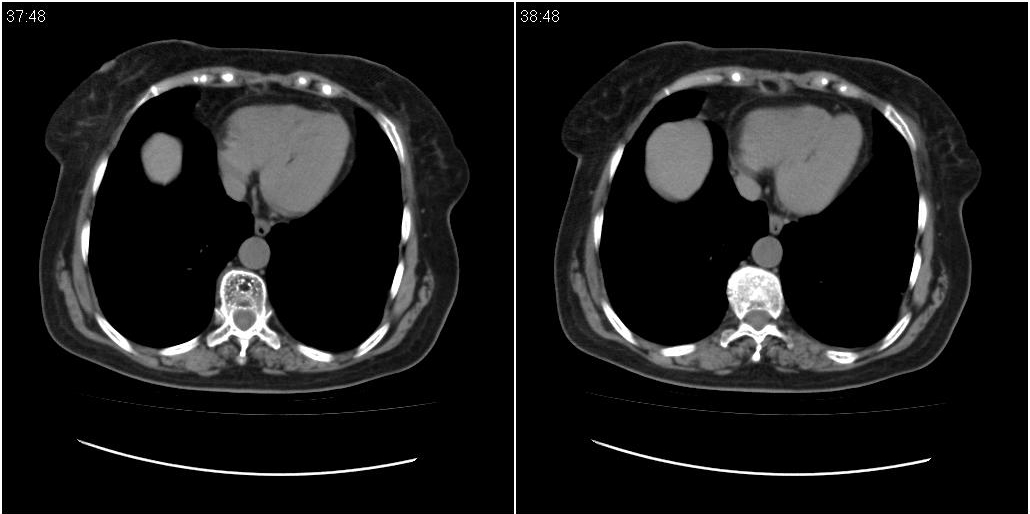

女性,72岁。去年9月份发现肺部病变,诊为肺结核并进行正规治疗至今,但复查后发现ct表现几乎没有变化。

双肺继发型tb并右中叶内膜tb,轻度支扩,左下胸膜肥厚粘连。

双肺继发性肺结核并右肺中叶节段性肺不张,左下胸膜肥厚粘连。

双肺继发性肺结核并右肺中叶节段性肺不张